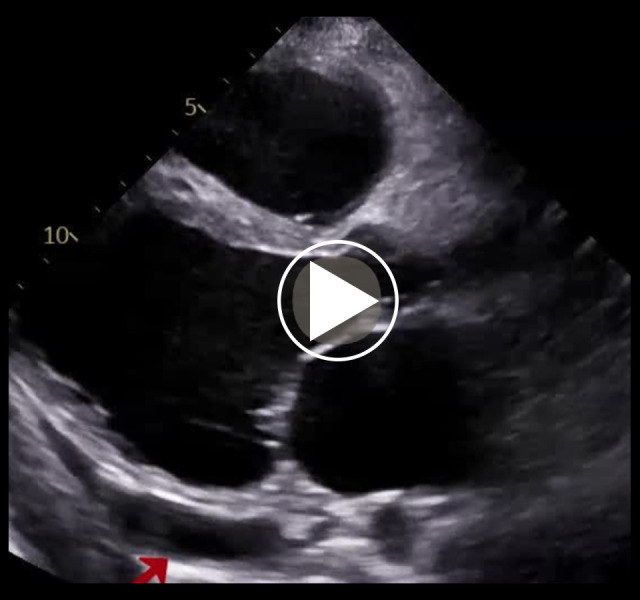

背景:卡恩斯-塞尔综合征(KSS)是一种罕见的遗传性线粒体疾病,以慢性进行性眼外麻痹、视网膜色素变性和心传导障碍为特征,发病年龄在20岁之前。该病还可表现为几种心血管(CV)疾病,如传导障碍或扩张型心肌病,并伴有神经肌肉和内分泌并发症。病例报告一名确诊为KSS的46岁男性在心脏移植(Htx)的鉴定过程中被心脏病研究所录取。患者的病史开始于诊断为三度房室传导阻滞,25岁时接受起搏器(PM)植入治疗。然而,由于左心室(LV)功能恶化的进展,PM在10年后升级为心脏再同步化除颤器治疗。入院前一年,患者因急性心力衰竭失代偿(ADHF)住院2次。入院时,体格检查显示充血特征。经胸超声心动图显示左室增大,整体运动功能减退,射血分数降低,右心室功能障碍。由于神经系统并发症和功能状况不佳,心脏小组同意对他进行保守治疗。由于ADHF的下一次住院治疗以患者死亡告终。结论:心血管疾病是治疗KSS患者的一个重要方面。我们的患者因并发症过度发展而转诊,因此他不能受益于Htx或机械循环支持。该病例强调了在并发症(包括心衰)完全发展之前对KSS患者进行早期诊断和监测的重要性。

BACKGROUND Kearns-Sayre syndrome (KSS) is a rare genetic, mitochondrial disorder characterized by a triad of chronic progressive external ophthalmoplegia, pigmentary retina degeneration, and cardiac conduction disorders, with onset before the age of 20 years. The disease can also manifest as several cardiovascular (CV) disorders, such as conduction disorders or dilated cardiomyopathy, along with neuromuscular and endocrinological complications. CASE REPORT A 46-year-old man diagnosed with KSS was admitted to the Institute of Heart Diseases in the qualification process for heart transplantation (Htx). The patient's medical history began with a diagnosis of third-degree atrioventricular block, treated with pacemaker (PM) implantation at age 25. However, due to progressing left ventricle (LV) function deterioration, PM was upgraded to cardiac resynchronization therapy with defibrillator 10 years later. In the year before the admission, he had undergone 2 hospitalizations caused by acute decompensations of heart failure (ADHF). Upon admission, physical examination revealed features of congestion. Transthoracic echocardiography showed an enlarged LV with global hypokinesia, reduced ejection fraction, and right ventricle dysfunction. Due to the neurological complications and poor functional condition, the Heart Team qualified him for conservative treatment. The next hospitalization due to ADHF ended in the patient's death. CONCLUSIONS CV disorders are an important aspect of treatment of KSS patients. Our patient was referred with excessively developed complications, so he could not benefit from Htx or mechanical circulatory support. This case highlights the importance of early diagnosis and monitoring of KSS patients before the full development of complications, including HF.